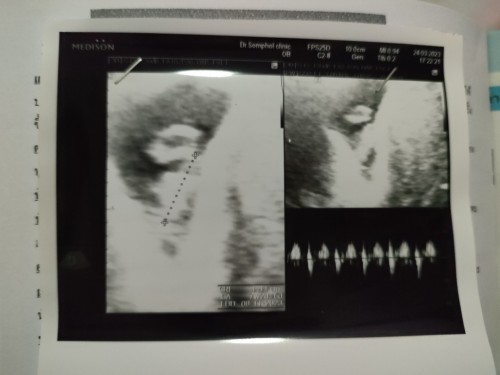

8week1day เจ้าหนูของแม่

เจอตัวและหัวใจน้องแล้ว แอบเก่งน่าดูกว่าจะเจอได้ ขอให้หนูแข็งแรง โตไวไวนะคะ คุณแม่ลูกสอง❤️🫄